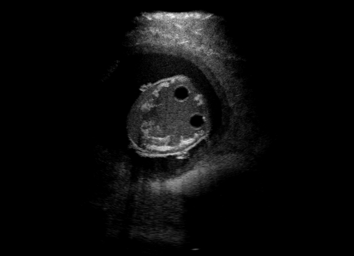

US simulation. We used a ray-tracing framework to render B-mode images from a geometric fetal model, by simulating a convex probe placed at multiple locations and orientations on the abdominal surface, with imaging settings listed in Tab 1. At each location, simply rasterizing a cross-section through the triangulated anatomical surfaces at the ultrasound center imaging plane provided corresponding semantic maps. Fig. 3 shows example B-mode images with corresponding semantic maps. A total of simulated frames were resized to and randomly split into training-validation-test sets by 80-10-10%.